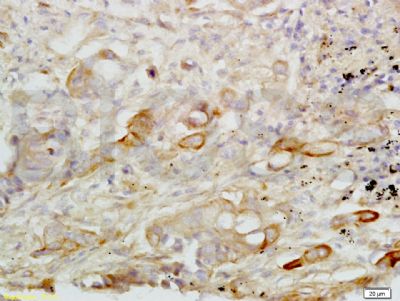

| 产品图片 |  Sample: BV2 Cell (Mouse) Lysate at 40 ug Primary: Anti- CXCL16 (bs-1441R) at 1/300 dilution Secondary: IRDye800CW Goat Anti-Rabbit IgG at 1/20000 dilution Predicted band size: 27 kD Observed band size: 27 kD  Tissue/cell: human lung carcinoma; 4% Paraformaldehyde-fixed and paraffin-embedded; Antigen retrieval: citrate buffer ( 0.01M, pH 6.0 ), Boiling bathing for 15min; Block endogenous peroxidase by 3% Hydrogen peroxide for 30min; Blocking buffer (normal goat serum,C-0005) at 37℃ for 20 min; Incubation: Anti-CXCL16 Polyclonal Antibody, Unconjugated(bs-1441R) 1:200, overnight at 4°C, followed by conjugation to the secondary antibody(SP-0023) and DAB(C-0010) staining  Images kindly provided by Dr. Denny Cottle from the publication, Fetal inhibition of inflammation improves disease phenotypes in Harlequin Ichthyosis.Formalin-fixed and paraffin embedded mouse skin probed with Rabbit Anti-CXCL16 Polyclonal Antibody (bs-1441R) at 1:50 for two hours at room temperature (green channel).  Paraformaldehyde-fixed, paraffin embedded (Rat colon); Antigen retrieval by boiling in sodium citrate buffer (pH6.0) for 15min; Block endogenous peroxidase by 3% hydrogen peroxide for 20 minutes; Blocking buffer (normal goat serum) at 37°C for 30min; Incubation: Anti-CXCL16 Antibody, conjugated (bs-1441R-AF488) at 1:100 overnight at 4°C; DAPI (5ug/ml, blue, C-0033) was used to stain the cell nuclei.  Blank control: A431. Primary Antibody (green line): Rabbit Anti-CXCL16 antibody (bs-1441R) Dilution: 3μg /10^6 cells; Isotype Control Antibody (orange line): Rabbit IgG . Secondary Antibody: Goat anti-rabbit IgG-AF647 Dilution: 3μg /test. Protocol The cells were incubated in 5%BSA to block non-specific protein-protein interactions for 30 min at at room temperature .Cells stained with Primary Antibody for 30 min at room temperature. The secondary antibody used for 40 min at room temperature. Acquisition of 20,000 events was performed. |